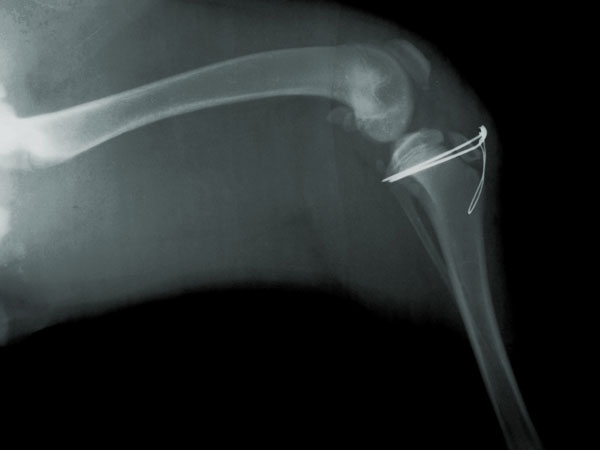

Φωτογραφίες πρίν και μετά το χειρουργείο.

Η αποκατάσταση του κατάγματος έγινε με τοποθέτηση 2 ήλων Kirschner και μεταλλικό ράμμα se tension band wire στην πρόσθια επιφάνεια

της κνήμης.